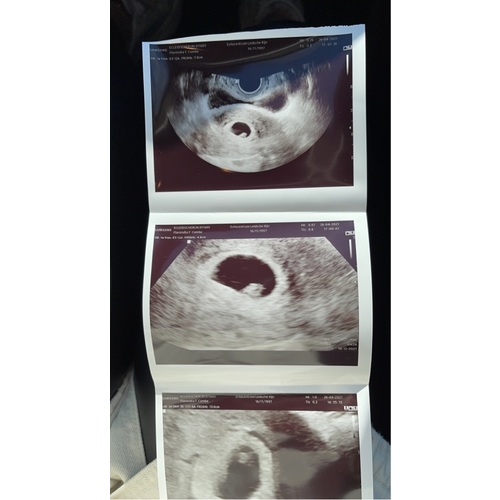

Ik heb pretecho gedaan met 6 weken

Ja dat kan ik had er al 1 bij 6 weken !

Ja ze hebben een foto uitwendig met volle blaas gemaakt was er wel wat te zien en een hartje en inwendig wat duidelijker !!

Ik had een inwendige echo (dan zien ze vaak meer). Ik ging er voor de zekerheid wel heen met een volle blaas, bij een inwendige echo kun je dan daar nog even naar de wc.